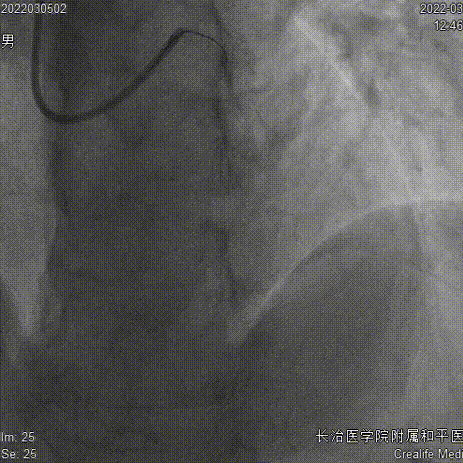

药物球囊2.75x35mm、Telescope™导引延长导管

药物球囊定位、释放

结果